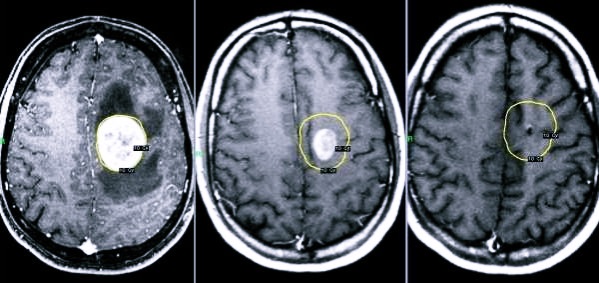

Диагностика

Постановка правильного диагноза – одна из важнейших составляющих лечения. При неправильном подходе есть риск летального исхода. Так, в случае, когда злокачественную опухоль путают с такой кистой, могут назначить проведение хирургической операции, чего делать ни в коем случае при опасных опухолях нельзя.

Сначала врач проводит опрос, составляя полную картину симптомов пациента. После этого обязательно назначаются КТ, МРТ и УЗИ, при этом последнюю процедуру проходить нужно с внутривенным введением контрастного вещества, что поможет определить злокачественная или доброкачественная опухоль у больного. Также врач назначает другие обследования, чтобы точно определить причину образования кисты. Важно сделать это сразу, чтобы быстро начать лечение и исключить повторное негативное воздействие первопричины.

Сразу после выявления расширения ретроцеребеллярного пространства и постановки диагноза больному назначается лечение. Необходимо приступить к нему максимально быстро, чтобы исключить дальнейшее ухудшение состояния и всевозможные риски.